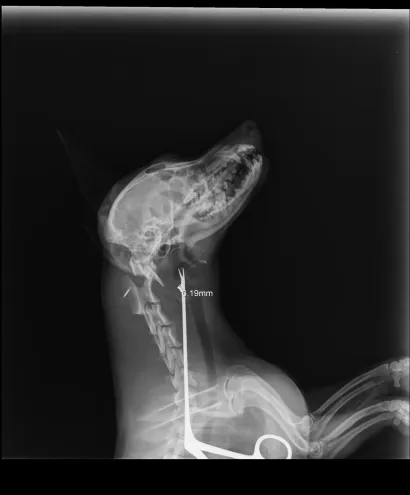

Maleni pas mješanac pogođen je dijabolom u vrat, a budući da je metak ostao smješten na nezgodnom mjestu blizu kralježnice, veterinar Mate Karaula iz Daruvara koji liječi Lenu, odustao je od vađenja metka zbog daljnjeg rizika po kujicu.

Prema nalazu veterinara dr. Mate Karaule, rendgenska snimka pokazala je da se metak, točnije dijabola, nalazi u području između atlasa i aksisa – dijela vratne kralježnice.

- Veličina projektila procijenjena je na 6,10 do 5,16 milimetara, a zbog dubine položaja i blizine kralježnice procijenjeno je da bi pokušaj vađenja mogao izazvati ozbiljne komplikacije. Zbog toga se odustalo od kirurškog vađenja metka.

Pas je primio injekcijsku sedaciju, obavljene su dvije rendgenske snimke i kirurška obrada rane, kazao nam je dr. Karaula.